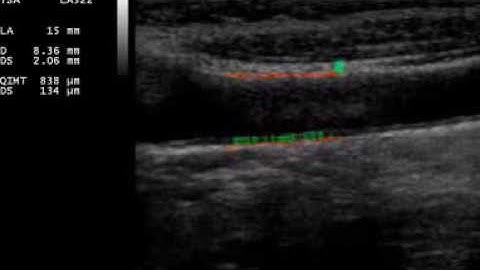

Fully automated segmentation, tracking of IMT in ultrasound video sequence of common carotid artery